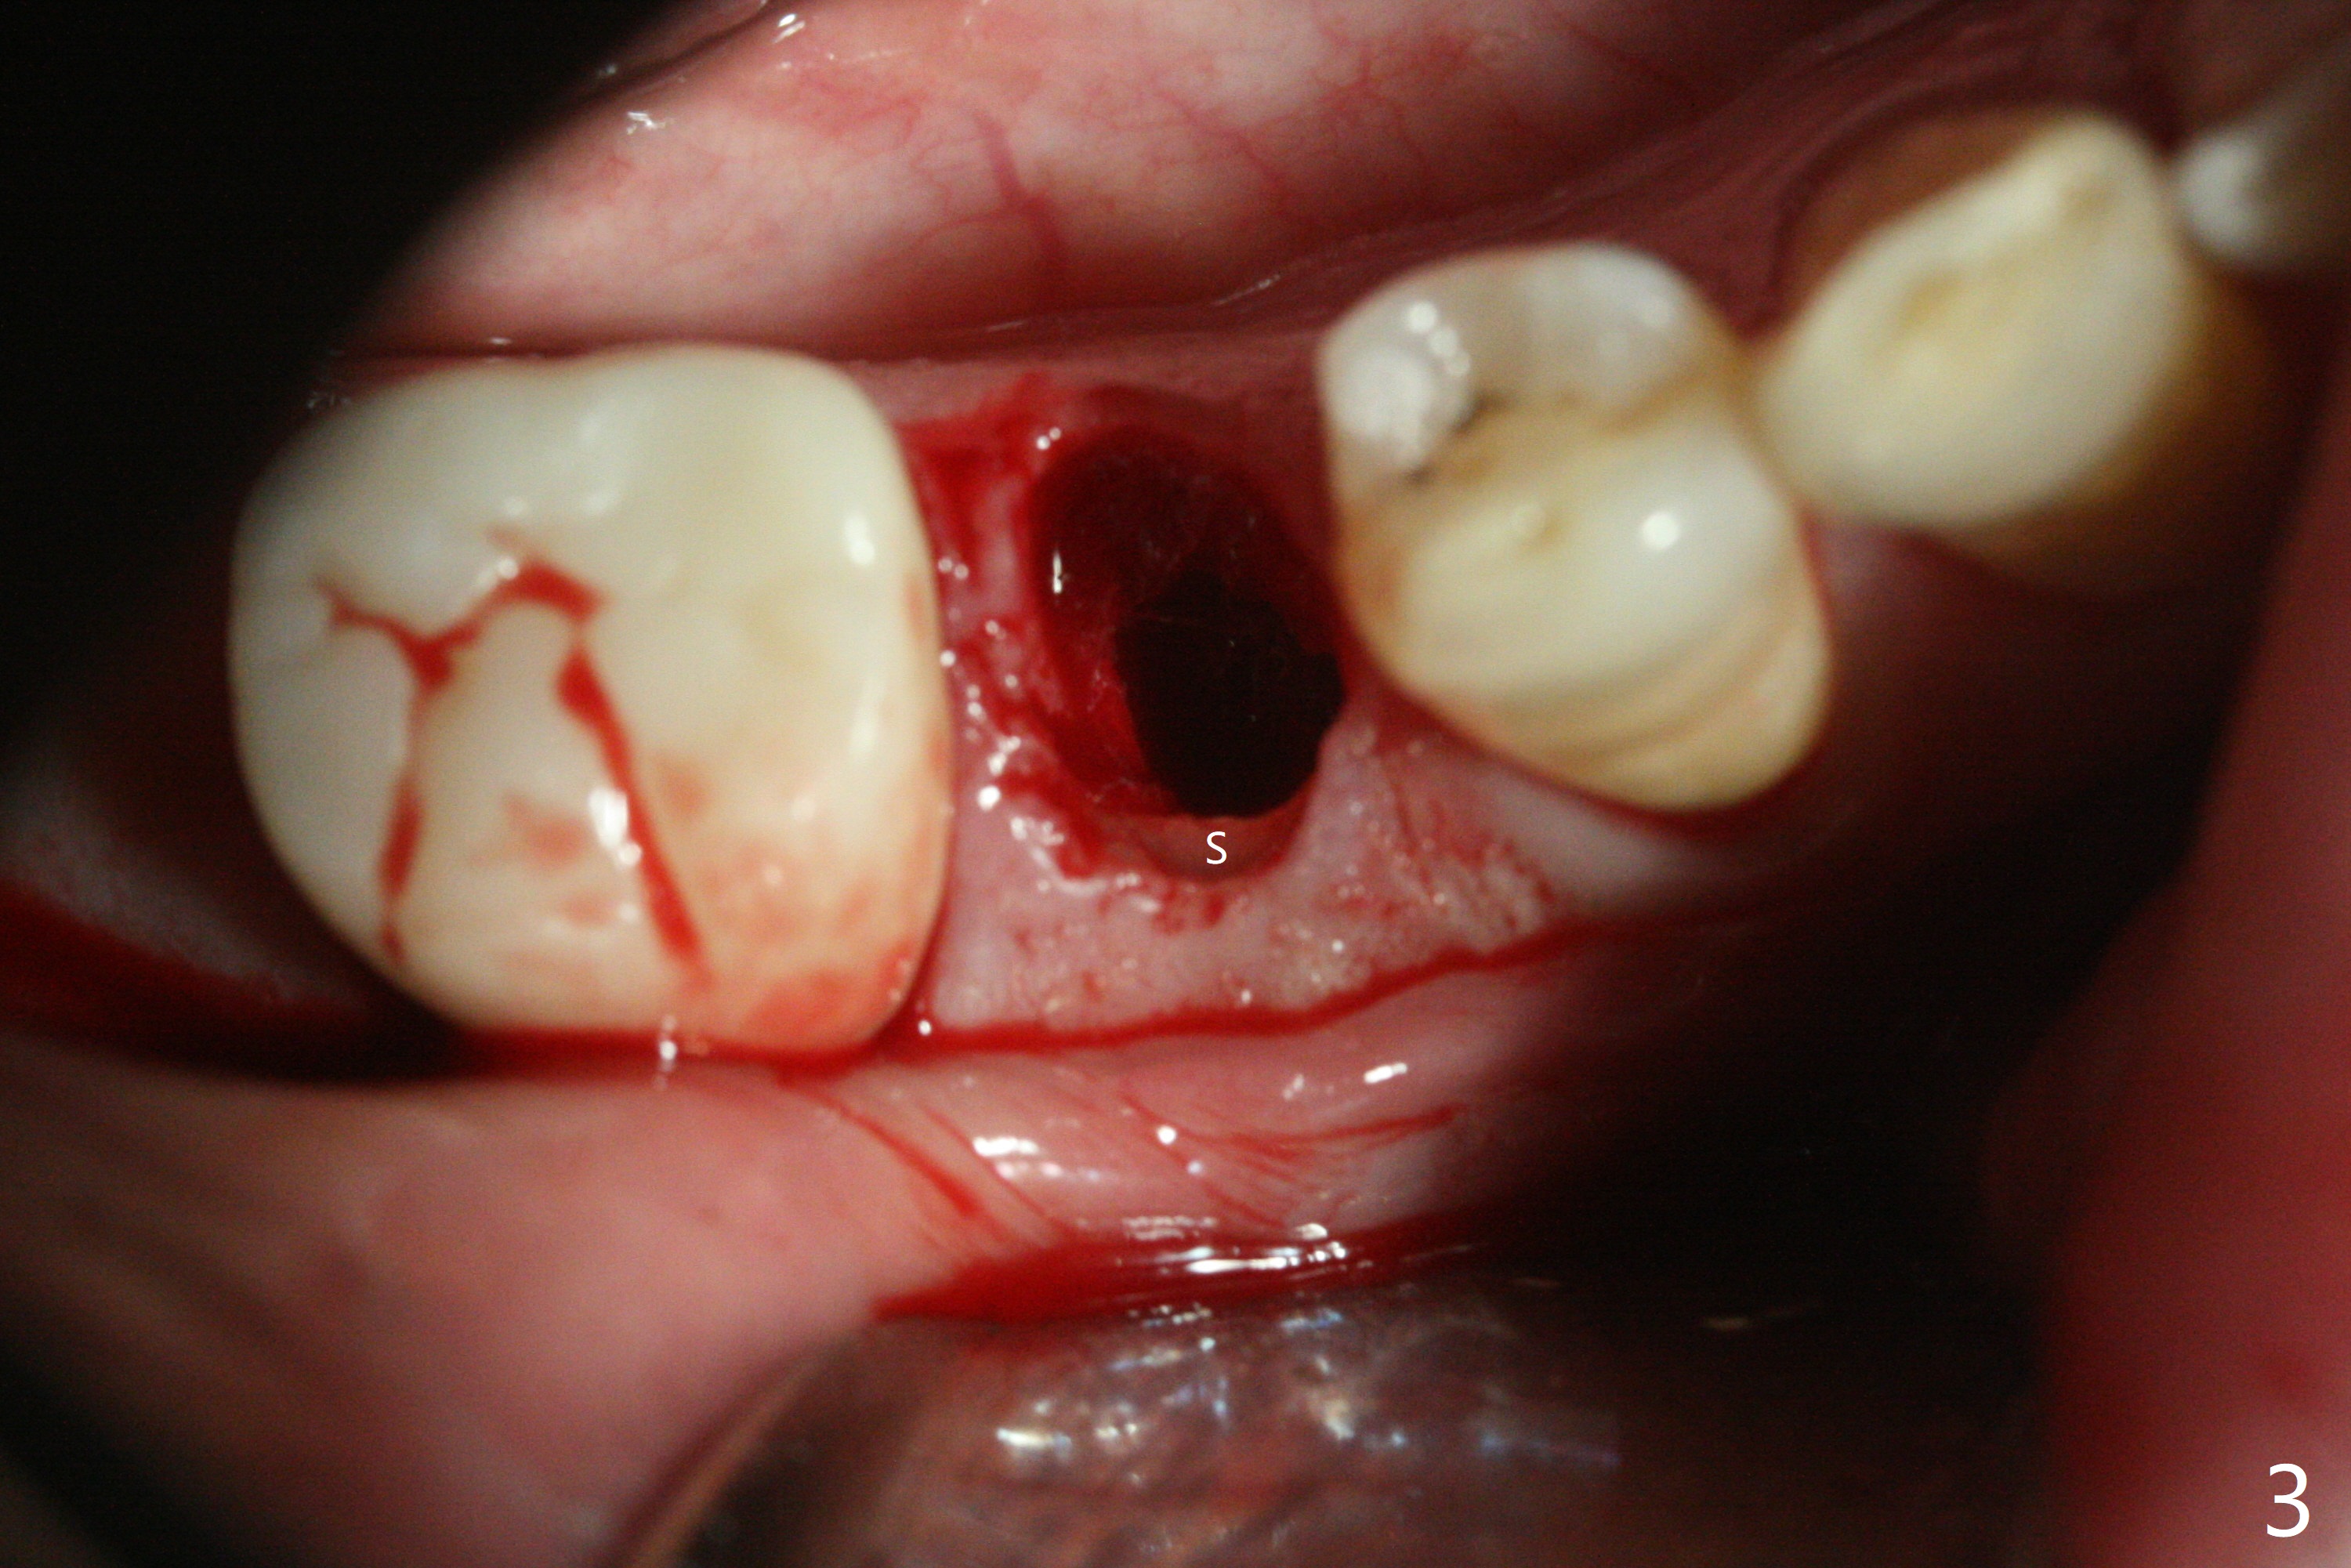

Since the root surface at #29 is distinct (Fig.1), while that at #21 is not (with subgingival caries, Fig.2), closed and open socket shields are done at #29 and 21, respectively (Fig.3,4 S), followed by implant placement with guide (Fig.4-6). With socket shield, there is limited remaining space for bone graft (Fig.4). The shield associated with the closed technique is exposed nearly 2 months postop (Fig.7), while the one associated with the open technique is not (Fig.8). The buccal plate is minimally atrophic with either technique.